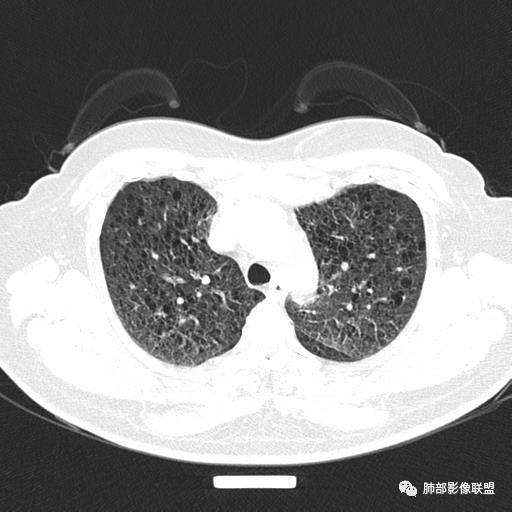

中年女性,不吸烟

双肺弥漫囊腔,累及肋膈角,囊腔形态相对规则单一。

CT平扫示双肺弥漫分布大小不等囊状薄壁透光区,无内、中、外带分布差异,间质稍示增厚。拟LAM

中年女性育龄期妇女,咳嗽气喘,无吸烟史,有苯吸入史。影像:双肺弥漫均匀小囊腔,无明显分布优势,囊腔形态欠规则,壁薄,部分囊腔边缘血管征,伴双肺弥漫磨玻璃影,无结节,考虑lam,鉴别苯中毒肺损伤,囊腔多有分布优势,小叶中心分布为主,形态规整等

女,46,活动性气喘1年。苯吸入史半年。胸部CT:两肺弥漫囊腔,上至肺尖,下至肋膈角,形态类似小囊腔。考虑:LAM,鉴别LIP,BHD,PLCH等。

双肺弥漫大小不一薄壁含气囊腔,囊间肺组织正常,正常肺背景,肺尖肺底受累;青年女性,气喘,支持LAM

CT表现:双肺弥漫大小不等的薄壁囊腔,囊壁<2mm,外形规则,血管影多位于囊腔周围,囊腔之间肺组织正常,随着疾病进展到晚期,囊腔变大、增多,不可胜数,囊腔可融合成较大的囊,与肺气肿相似,形成间质性肺纤维化。部分病例可出现结节影。